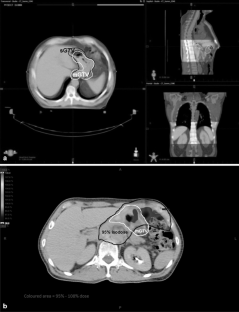

Imaging of 6 patients was explored prospectively. Intensity-modulated radiotherapy (IMRT) planning was based on 4D/3D imaging of computed tomography (CT) and positron-emission tomography (PET)-CT. Static and motion gross tumor volume (sGTV and mGTV, respectively) were distinguished by defining GTV (empty stomach), clinical target volume (CTV = GTV + 5 mm margin), PTV (GTV + 10/15/20/25 mm margins)  plus paraaortic lymph nodes and proximal duodenum. Overlap of 4D-Listmode-PET-based mCTV with 3D-CT-based PTV (increasing margins) and V95/D95 of mCTV were evaluated. Gastric shifts were determined using online cone-beam CT. Dose contribution to organs at risk was assessed.

The 4D data demonstrate considerable intra-/interfractional variation of the stomach, especially along the vertical axis. Conventional 3D-CT planning utilizing advancing PTV margins of 10/15/20/25 mm resulted in rising dose coverage of mCTV (4D-Listmode-PET-Summation-CT) and rising D95 and V95 of mCTV. A PTV margin of 15 mm was adequate in 3 of 6 patients, a PTV margin of 20 mm was adequate in 4 of 6 patients, and a PTV margin of 25 mm was adequate in 5 of 6 patients.